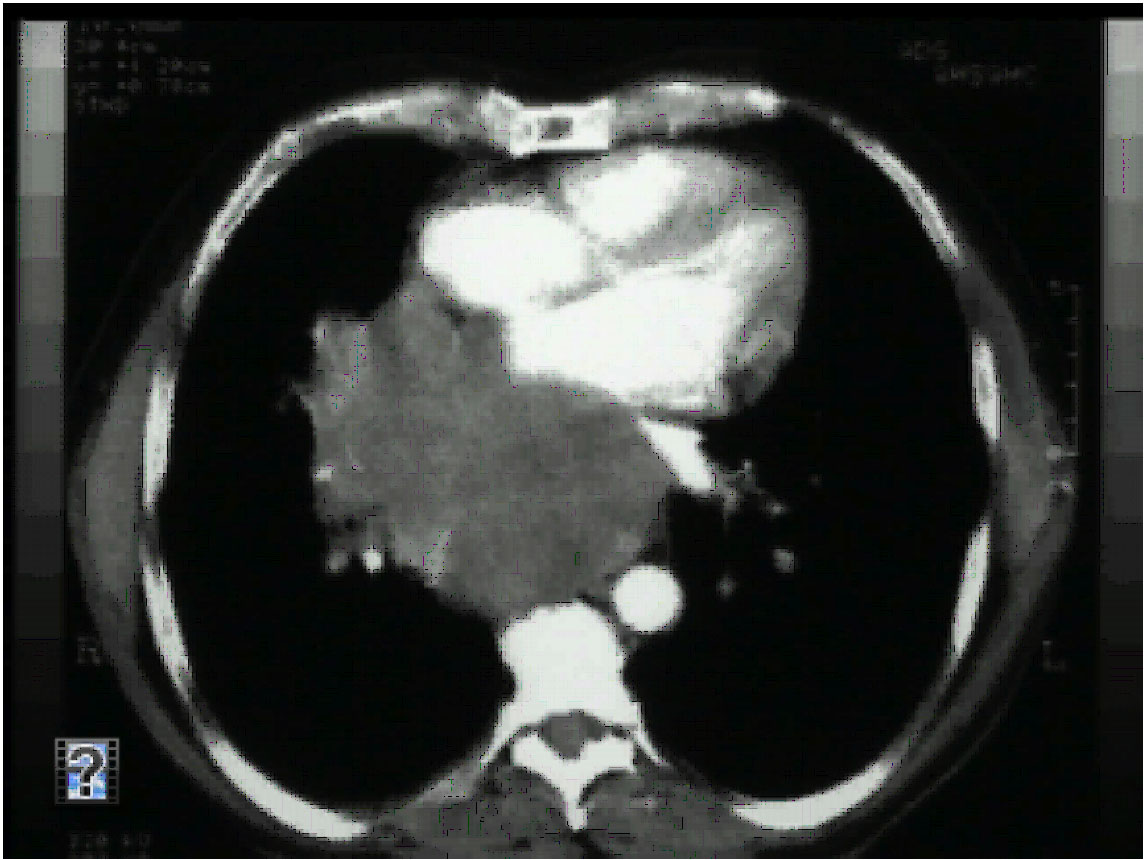

Figure 36 : Scanner thoracique : Tumeur broncho pulmonaire envahissant les oreillettes (flèche)

En cardiologie, il est très utilisé pour l’examen des gros vaisseaux thoraciques et le diagnostic de leurs pathologies, (anévrysmes, dissections, embolies pulmonaires) notamment dans le cadre de l’urgence.